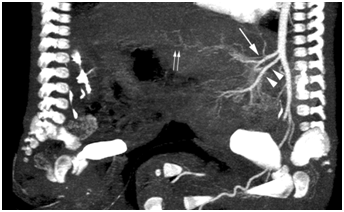

In the early phase, the anatomy of the arterial vasculature was delineated clearly. Due to rapid blood circulation, the portal vein was also demonstrated. In Twin A, the celiac trunk and superior mesenteric artery branched off the abdominal aorta in the proper order (Figure 2). No blood flow from Twin A’s superior mesenteric artery was observed in Twin B, ruling out small intestinal conjunction. The proper anatomy of the branches of the celiac artery and portal vein in Twin A was confirmed. The fused lobe of the liver in Twin B showed an enhanced portal vein that communicated with that of Twin A (Figure 3). In Twin B, the fused lobe was enhanced secondary to crossover circulation in the delayed phase (Figure 4). The fusion area was seen as an irregular strip. No definite enhancement in the other area of liver in Twin B was seen. The entire liver of Twin A was enhanced.

Figure 2 Sagittal MPVR image of early-phase CT shows the celiac trunk (arrow) and superior mesenteric artery (arrowhead). Portal venous communication with the other baby was seen (double arrows).